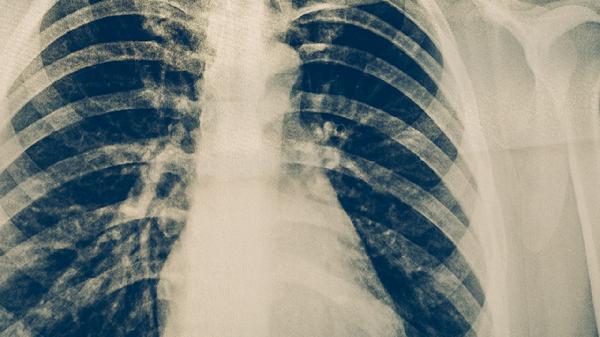

結(jié)核性胸膜炎是肺結(jié)核最常見的并發(fā)癥,表現(xiàn)為胸痛、呼吸困難及胸腔積液。結(jié)核分枝桿菌侵犯胸膜后引發(fā)炎癥反應(yīng),滲出液積聚形成胸腔積液。診斷需結(jié)合胸部X線或CT檢查,治療需在抗結(jié)核基礎(chǔ)上聯(lián)合胸腔穿刺引流,常用藥物包括異煙肼片、利福平膠囊和吡嗪酰胺片。

骨結(jié)核好發(fā)于脊柱和髖關(guān)節(jié),表現(xiàn)為局部疼痛、活動受限及寒性膿腫。椎體破壞可導(dǎo)致截癱,影像學(xué)可見骨質(zhì)破壞和椎間隙狹窄。治療需固定患肢并聯(lián)合異煙肼片、利福平膠囊和鏈霉素注射液,膿腫形成需手術(shù)清創(chuàng)。